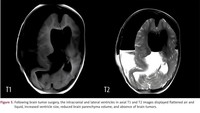

Dalam kasus yang sangat langka, dokter di China melakukan operasi pengangkatan janin dari dalam otak bayi berusia 1 tahun. Janin tersebut merupakan kembaran diamniotik monokorionik dari anak tersebut, berarti janin berasal dari sel telur dan plasenta yang sama, tapi berkembang di kantung ketuban terpisah. (Foto: American Journal of Case Reports)